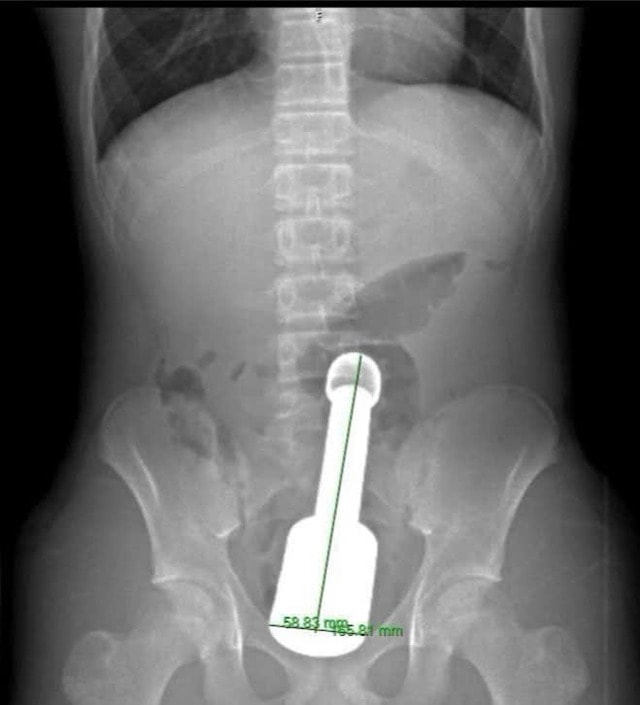

Bệnh nhân nhập viện trong tình trạng đau tức dữ dội vùng hạ vị. Kết quả chẩn đoán hình ảnh cho thấy một dị vật kim loại lớn mắc kẹt sâu trong trực tràng, gây chèn ép các cơ quan vùng chậu. Đây là tình huống nguy hiểm, dễ dẫn đến biến chứng nặng nếu không xử trí kịp thời.

Dị vật là một chiếc chày dài 18cm, đường kính 6cm. Thử thách lớn nhất đối với kíp mổ là dị vật quá to so với cơ thắt hậu môn của thiếu niên, đồng thời tạo ra "hiệu ứng chân không" khiến nó bị hút chặt vào lòng ruột.